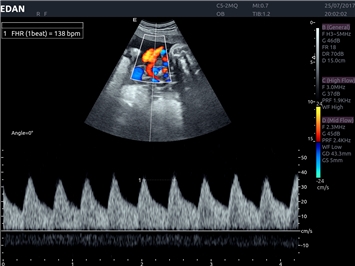

EDAN Acclarix LX4 представляет собой инновационную ультразвуковую систему, построенную на усовершенствованной платформе Acclarix. Сочетание высокого качества визуализации с интеллектуальным рабочим процессом делает эту систему оптимальным выбором для клиник, ценящих эффективность и экономичность.

• Акушерства и гинекологии

Импульсно-волновой допплер:

Да

Триплексное сканирование: